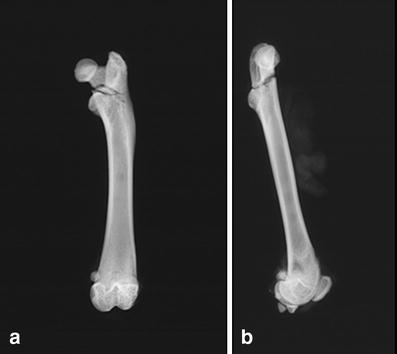

Radiographs of proximal rat femur after breaking test. We observed in 86.6% of cases (in right–left comparison) a reverse trochanteric fracture (type A3 according to AO classification; a anterior–posterior view, b lateral view)

We also observed this fracture type in our comparative bioassay of OVX rats (n = 44). In the comparative bioassay (sham, C, E, PTH), we observed in four cases a tilt of the femoral head during the breaking test due to an inaccurate breaking curve. These cases were not taken into consideration. We presented here data only in femurs (88.6%) with trochanteric fractures (39 from 44 fractures).

In our study, the reproducibility of the biomechanical test of the rat femurs was determined by comparing the data from the right and left femurs of the non-OVX rats. Our new breaking test yielded no significant systematic differences concerning the mechanical characteristics of the right and left femurs. Side comparative studies in human and animals show intraindividual variations of the same dimension that are found in our right–left comparison. In humans, we know there are differences (up to 15%) in size and strength of the right and left lower extremity (anklebone) or upper extremity (right- or left-handed person) [15]. The analysis of the fracture type producing in our breaking test showed in the right–left-comparison test in 86.6% and in the biocomparative assay in 88.6% of the animals a reversed trochanteric fracture of femur (type A3 according to the AO classification). These results demonstrate the high reproducibility of our new mechanical testing method.